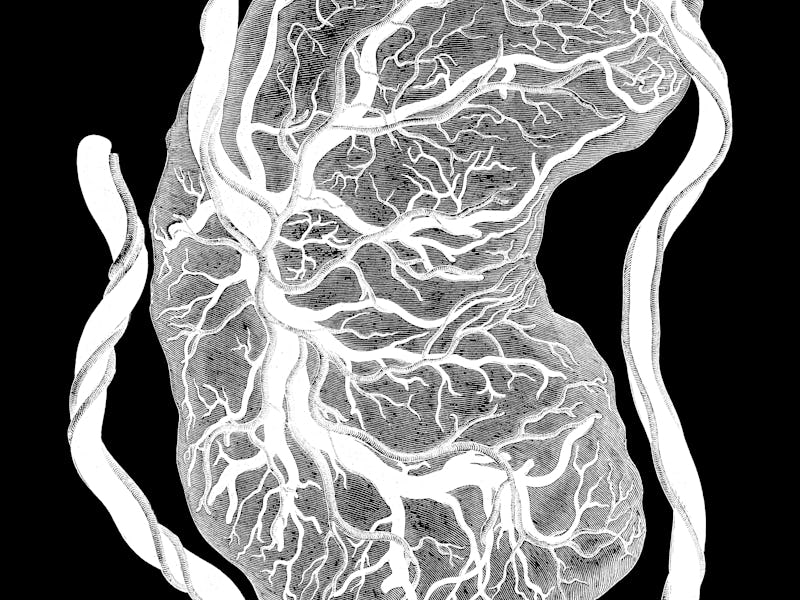

The human placenta does a lot of work for the fetus; it is, effectively, the fetal lungs, kidneys, and digestive tract. It’s also one of the only organs in the animal world that consists of two separate organisms — with tissues from both the mother and fetus — as well as the only temporary organ.

The placenta evolves across a pregnancy, too, continuing to support the developing fetus while interacting with the maternal environment, said Weinberg. The research has, so far, shown that issues with the placenta — its size, its placement, its microbiome — can signal health problems with both pregnant person and fetus, such as preeclampsia, gestational diabetes, preterm birth, and stillbirth.